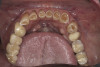

(15.) Preoperative maxillary, occlusal view.

Figure 15